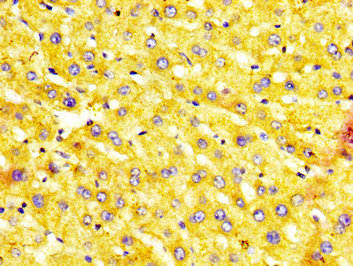

IHC image of CSB-PA015055LA01HU diluted at 1:400 and staining in paraffin-embedded human liver tissue performed on a Leica BondTM system. After dewaxing and hydration, antigen retrieval was mediated by high pressure in a citrate buffer (pH 6.0). Section was blocked with 10% normal goat serum 30min at RT. Then primary antibody (1% BSA) was incubated at 4°C overnight. The primary is detected by a biotinylated secondary antibody and visualized using an HRP conjugated SP system.